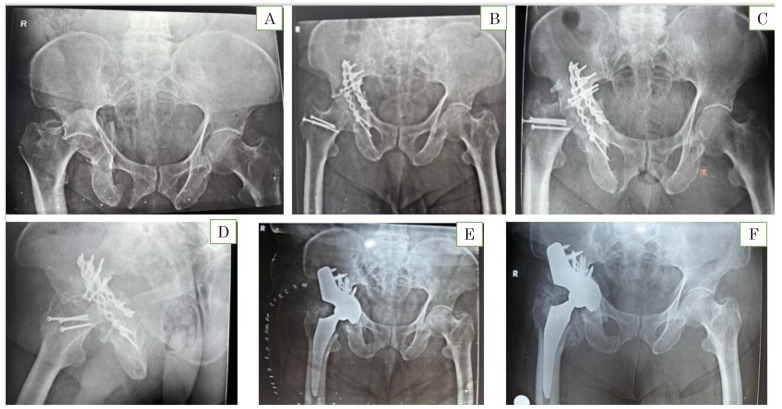

Materials and methods: This longitudinal comparative study, which included 40 patients who underwent THR for either posttraumatic arthritis after fixation of an acetabular fracture or arthritis following conservative management of a fracture, was conducted for 60 months. Twenty-four patients had undergone ORIF, and 16 patients had undergone nonoperative/conservative management for acetabular fractures. Following THR, the patients were followed up for monitoring of functional outcomes for the Harris hip score (HHS) and comparison between the ORIF and non-ORIF groups was performed.

Results: The HHS showed significant improvement in both ORIF and non-ORIF groups. At the end of the mean follow-up period, no significant variation in scores was observed between the groups, i.e., ORIF group (91.61±6.64) compared to non-ORIF group (85.74±11.56). A significantly higher number of re-interventions were required for medial wall fractures and combined fractures compared to posterior fractures (P<0.05).

Conclusion: THR resulted in improved functional outcome during follow-up in both the groups; however, the ORIF group was observed to have better functional outcome. Re-intervention was not required for any of the posterior fractures at the end of the mean follow-up period.